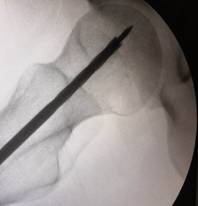

術(shù)中,為患者打通“隧道”,注入血小板

經(jīng)過術(shù)前與麻師團隊詳盡的討論及預(yù)案制定后,手術(shù)醫(yī)師首先為吳先生實施雙側(cè)股骨頭壞死髓芯減壓,即打開一個像筷子大小的“隧道”孔后,再通過“隧道”將分離的血小板注射進吳先生骨頭壞死區(qū)域。整個手術(shù)僅抽取了80毫升血液,耗時數(shù)十分鐘,術(shù)后三天患者出院。